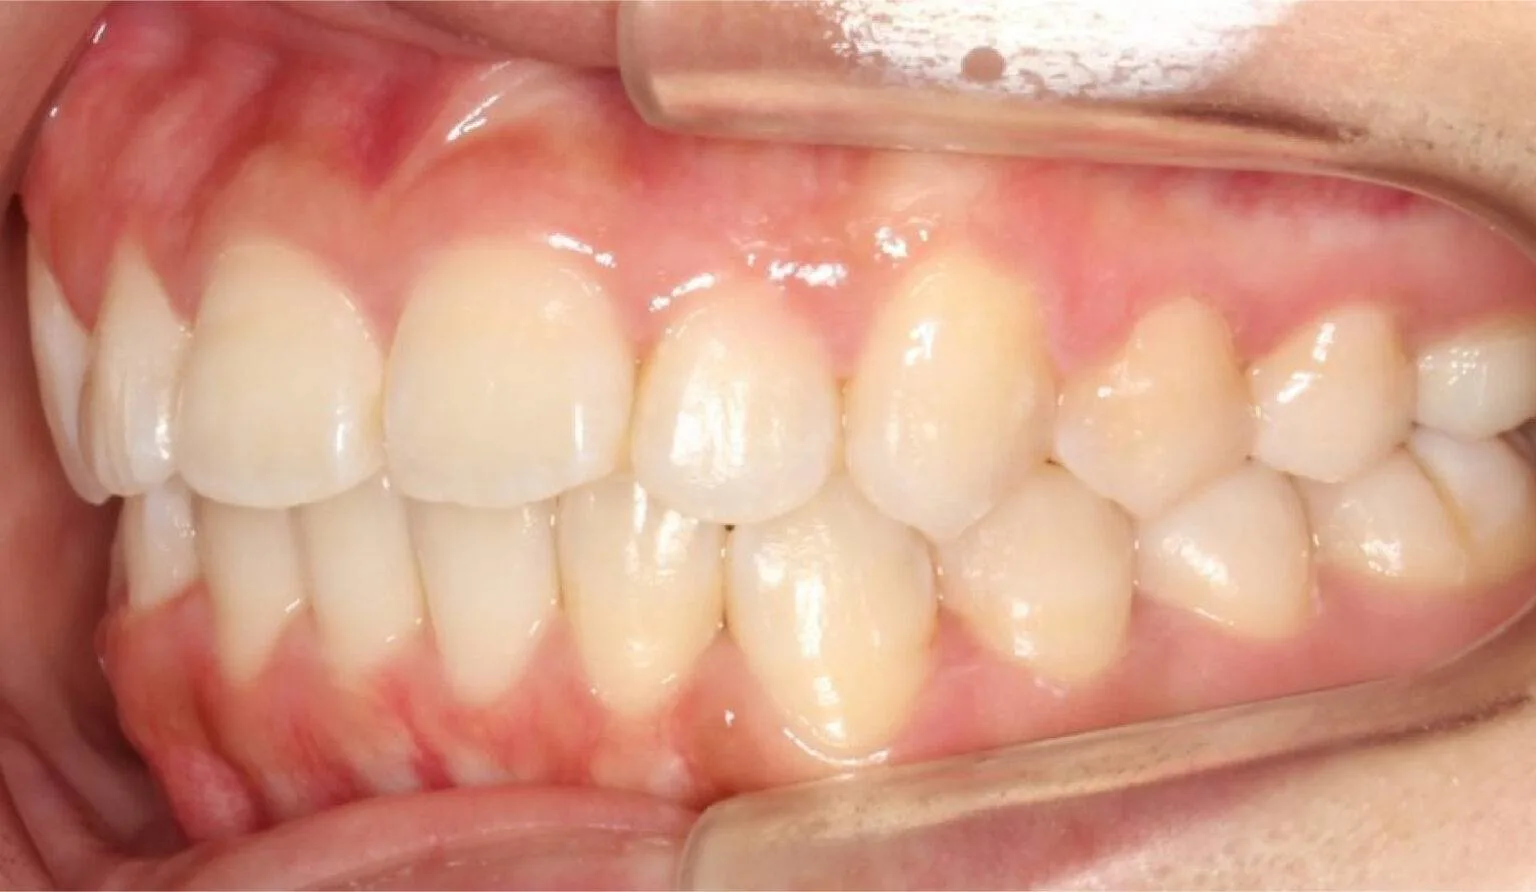

Overcrowding is a common teeth misalignment which occurs due to lack of space in the oral cavity for the teeth. This makes the teeth grow to be crooked and/or overlap with each other. This creates an overcrowded atmosphere in the mouth and can lead to poor oral hygiene due to the inability to clean the teeth efficiently.

This is where the upper teeth horizontally protrude past the bottom teeth, also called an ‘Overbite’. A common dental complaint we hear that relates to protrusion is ‘my front teeth are sticking out’.

The protrusion of teeth can cause speech problems and make it difficult to consume food, this is due to the fact it can prevent correct biting and chewing.

Protrusion is a dental condition that is usually caused by skeletal issues with the lower jaw, mainly in those who have a growth deficiency. Overbites can cause irreparable soft tissue damage and also contribute to early tooth loss from excessive wear of the teeth. Besides overjets having functional side effects, they can also affect the aesthetics of the smile. Overall, it can look unpleasant to the eye, this can affect a person’s psychological and emotional state.

This is when the upper teeth bite down on the insides of the lower teeth, this can also be known as a negative overjet. Common dental complaints we hear that relate to a crossbite are “my chin protrudes out”, “my front teeth bite on each other” or “I can’t bite on my back teeth properly”.

A crossbite can happen on either side of the jaw and it affects both the front and back teeth. Crossbites usually occur due to a dental or skeletal problem, or both. These can be caused by habits, bone structure, airway issues, or genetics. Untreated crossbites can affect more than just the teeth, they can cause issues in the jaw. It makes the jaw muscles work at an uneven rate, which causes temporomandibular joint disorder, it can cause headaches and pain in the jaw, neck, or shoulders.